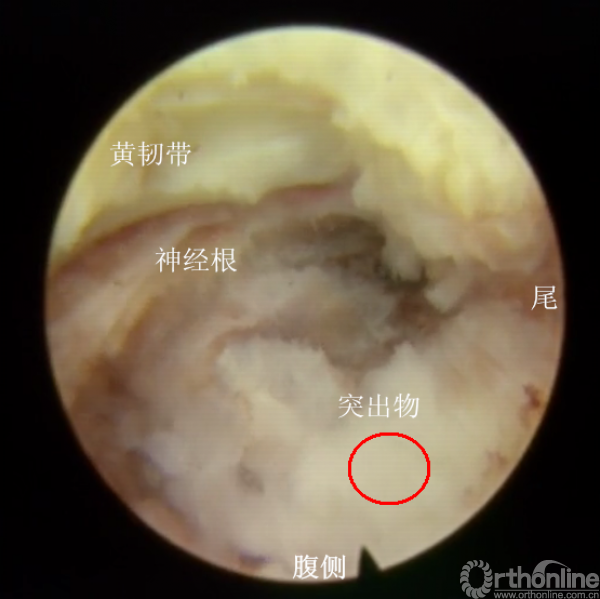

镜下成型后,已经能够看到突出物的尾端

拖拽尾端,仅取出部分,且见突出物卡压明显

取出部分尾端后,仍有残留,且神经根卡压

咬除部分黄韧带,再次减压后见结构清晰

但见神经根远端波动仍然不明显,且尾侧见有卡压物

工作套管往尾端移后,见一突出物,且相应节段的神经根波动差

逐步减压后,取出突出物后,见整个走行的神经根波动明显